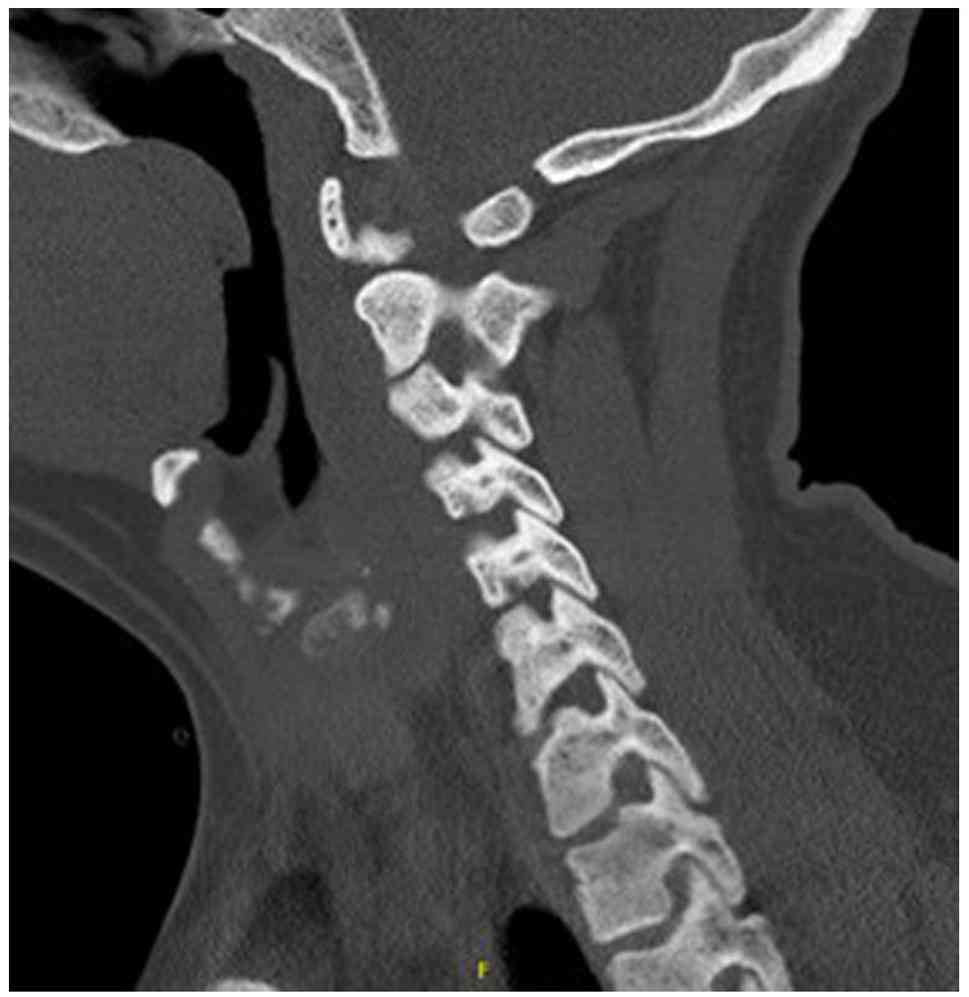

Upon arrival, he was hypotensive and symptomatic. An electrocardiogram (Fig. 1) demonstrated sinus rhythm with peaked T waves. Laboratory results revealed hyperkalemia, elevated levels of troponins (in thousands; ng/l), acute kidney injury and high anion gap metabolic acidosis. Urine drug screening yielded negative results, while salicylate and acetaminophen levels were normal. Other laboratory results are listed in Table I. Imaging analyses, including a computed tomography scan of the cervical spine (Fig. 2), and chest, abdomen and pelvis (Fig. 3), revealed diffuse bony sclerosis.

Computed tomography scan of the

cervical spine without IV contrast illustrating generalized

osteosclerosis.

Figure 2

Computed tomography scan of the cervical spine without IV contrast illustrating generalized osteosclerosis.

Inhalant-related skeletal fluorosis can produce diffuse osteosclerosis, trabecular coarsening, cortical thickening and soft-tissue ossifications, with imaging serving as the most sensitive diagnostic tool. As fluoride accumulates in bone with a long half-life, radiographic changes may persist for years even after exposure stops (15). In the patient in the present study, extensive osteosclerosis was evident despite his young age, consistent with chronic hydrofluorocarbon exposure, although a DEXA scan was not obtained. However, in the present study, serum or urine fluoride levels were not measured to confirm fluorosis; thus, this is a limitation of the present study. Without fluoride quantification, a definitive diagnosis of skeletal fluorosis cannot be made. Instead, toxic-metabolic bone disease from inhalant exposure was considered more likely. The differential diagnosis for diffuse osteosclerosis is limited, but includes osteoblastic metastases (e.g., prostate and breast), sclerotic myeloma, myelofibrosis, mastocytosis, Paget's disease and rare granulomatous disorders, such as sarcoidosis. In the case described herein, malignancy and myeloma were investigated and excluded, and there was no evidence of systemic diseases (such as sarcoidosis) that may cause similar bone changes.